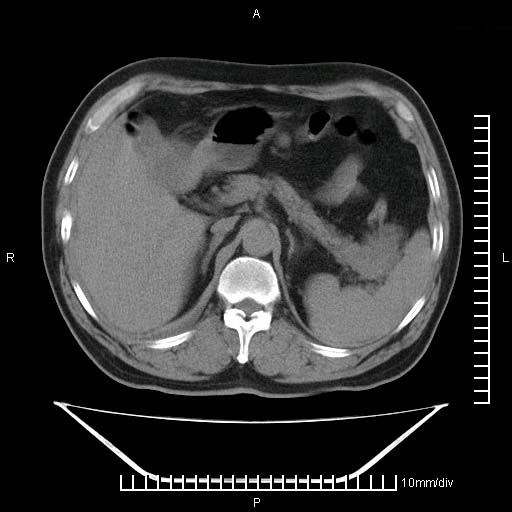

标题: CT25082:肝脏增强:男性,70岁 [打印本页]

标题: CT25082:肝脏增强:男性,70岁

患者以心脏疾病收住院,腹部无明显症状,b超查肝脏有占位。

增强效果不理想。考虑转移,胆囊壁明显增厚,不排除胆囊癌肝转移。

牛眼征,中心坏死无强化,外缘强化,最外缘又见低密度,考虑转移,与脓肿鉴别

肝内多发转移瘤,右下肺炎症并少量胸水。胃壁增厚建议胃镜,胰尾部“病变”为肠管。

1)肝脏多发性转移瘤(不排除胰尾癌转移所致可能)。2)腹水。3)右侧少量胸腔积液。

ct25082 结果:转移瘤

外院mr结果:胰尾恶性占位。